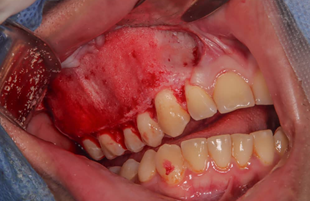

Una vez expuesta la superficie del hueso, se procede a realizar las líneas guía con pieza de mano de alta velocidad y fresa quirúrgica 702, tomando en consideración las mediciones de trabajo obtenidas mediante el cone beam realizadas por la residente y el Adjunto Cirujano Maxilofacial, detalladas en la historia clínica del paciente en el postgrado de Cirugía Bucal ULAC-IDOLA. (Figura 8) (Tabla 1)

Figura 8. Tallado de guías para el desgaste del tejido displásico usando pieza de mano de baja velocidad y fresa tipo pimpollo.

Fuente: Historia Clínica Postgrado Cirugía bucal ULAC-IDOLA Julio 2021

Una vez obtenido el patrón de desgaste, se procede a realizar el shaving utilizando pieza recta de baja velocidad con fresa tipo pimpollo de carburo – tungsteno, vástago HP, diámetro 080 en forma de llama con ángulo de corte negativo. De acuerdo a la percepción de los operadores mediante el tacto epicrítico, se logró la mayor simetría posible tomando en consideración el lado contralateral (Figura 9).

Figura 9. Se observa el resultado del desgate, previo a la reposición del colgajo y sutura.